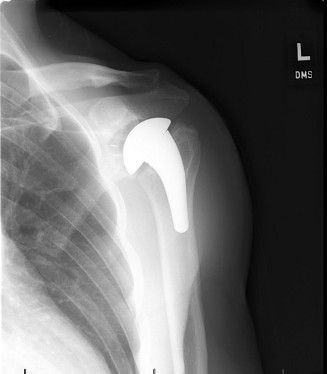

A 72-year-old, right-hand-dominant male with a history of type 2 diabetes, hypertension, and coronary artery …